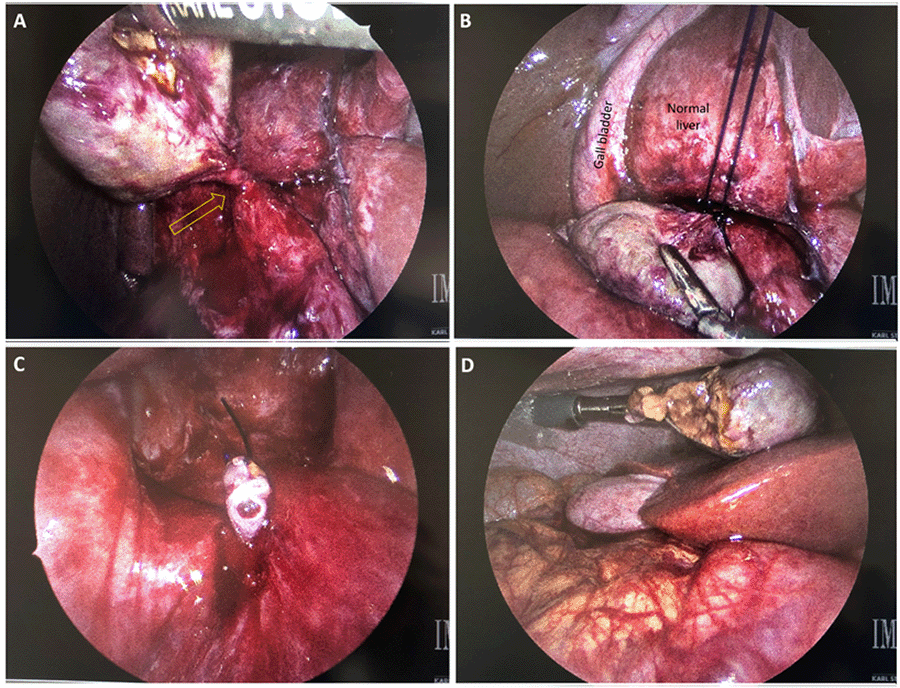

The patient was re-admitted five days later with continued symptoms. Given the family history of peptic ulcer disease and the possibility that this contained a perforation from a duodenal ulcer, the patient tested negative for Helicobacter pylori. An esophagogastroduodenoscopy was also obtained and was negative for ulcer disease. The following day he was taken to the operating room for diagnostic laparoscopy. After port placement, the liver was retracted cephalad, and a mass in the sub-hepatic space marginally inferior to segment 4B was identified. There was evidence of inflammation in the area. The mass was bluntly freed from the liver until the mass was only attached by a torsed stalk extending down to the area of the portal triad (Figure 2). The stalk was approximately 2 cm long and thin. We did not attempt to dissect this further to clarify the origin. An endoloop polydioxanone suture was used to ligate the stalk prior to transection. The mass was then placed in a retrieval bag and removed. On gross inspection, the mass was firm and well-circumscribed.

Figure 2. Laparoscopic Images. Published with Permission

A) Mass elevated with grasper demonstrating torsed pedicle. B) Endoloop suture passed around pedicle with mass retracted inferiorly; C) thrombosed lumen of pedicle. D) In situ view of specimen (with small area of torn capsule).